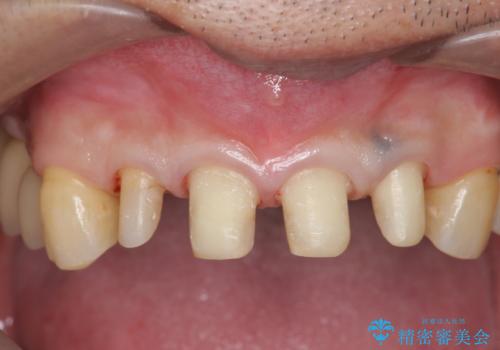

虫歯のマイクロスコープによる丁寧な除去、根管治療、深い虫歯に対する挺出(エクストリュージョン)および歯周外科を行ったのち精度の高いセラミッククラウン製作治療を計画します。

虫歯の放置により、根管治療や深い虫歯に対する処置が必要になりましたが丁寧に一つづつ処置を行ったことで抜歯をすることなく歯を残すことができました。

セラミッククラウンの製作をする前に、歯内・歯周環境の整備は非常に大切です。